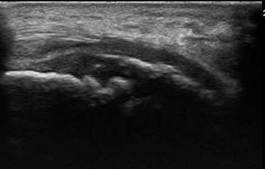

Kinder-echo van Sever Schinz (apofysitis calcanei)

Sever-Schinzpijn, ook wel apofysitis calcanei, is een groeipijn aan de achterkant van het hielbeen die vaak voorkomt bij actieve kinderen. De plek waar de achillespees aan het hielbeen hecht, raakt hierbij gevoelig en geïrriteerd. Met echografie kunnen wij goed zien of deze groeischijf ontstoken is en of er sprake is van overbelasting. Zo kunnen we een kindvriendelijk en passend advies geven om de klachten te verminderen.